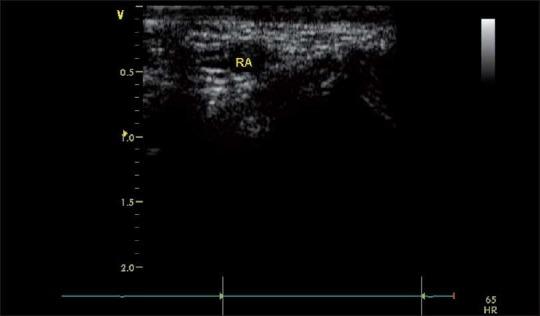

Over the last few years the role of ultrasound has steadily increased and has now an established role in anesthesia and critical care. The various applications of this technology in this field include ultrasound-guided insertion of central lines (internal jugular, subclavian, axillary, femoral) and peripheral venous catheters, arterial line insertion, regional blocks etc. The simple reason of using this technology is "You believe what you see". In this text we will mainly focus on central line, peripheral venous placement and arterial blood flow patterns under ultrasound guidance.In our institution at KFMC, internal jugular vein cannulation is preferred to cannulation of the subclavian vein because of the higher incidence of pneumothorax and subclavian artery puncture associated with the later. The incidence of carotid artery puncture is higher in children younger than five years than in older children during this procedure. The use of ultrasonography has been shown to increase the success rate and decrease the incidence of complications associated with IJV cannulation in adults. We will go through a stepwise approach in identifying and confirming the required blood vessels for ultrasound-guided cannulation using B-mode (2D), color flow doppler and Pulse Wave Doppler.

在过去几年中,超声的作用稳步增强,如今在麻醉和重症监护领域已确立了其地位。该技术在这一领域的各种应用包括超声引导下置入中心静脉导管(颈内静脉、锁骨下静脉、腋静脉、股静脉)和外周静脉导管、动脉置管、区域阻滞等。使用这项技术的简单原因是“眼见为实”。在本文中,我们将主要关注超声引导下的中心静脉置管、外周静脉置管以及动脉血流模式。在我们位于科威特法赫德国王医疗城的机构中,由于锁骨下静脉置管相关的气胸和锁骨下动脉穿刺发生率较高,因此颈内静脉置管比锁骨下静脉置管更受青睐。在此操作过程中,5岁以下儿童的颈动脉穿刺发生率高于大龄儿童。超声检查已被证明可提高成人颈内静脉置管的成功率并降低相关并发症的发生率。我们将采用逐步的方法,使用B超(二维)、彩色多普勒血流显像和脉冲波多普勒来识别和确认超声引导下置管所需的血管。